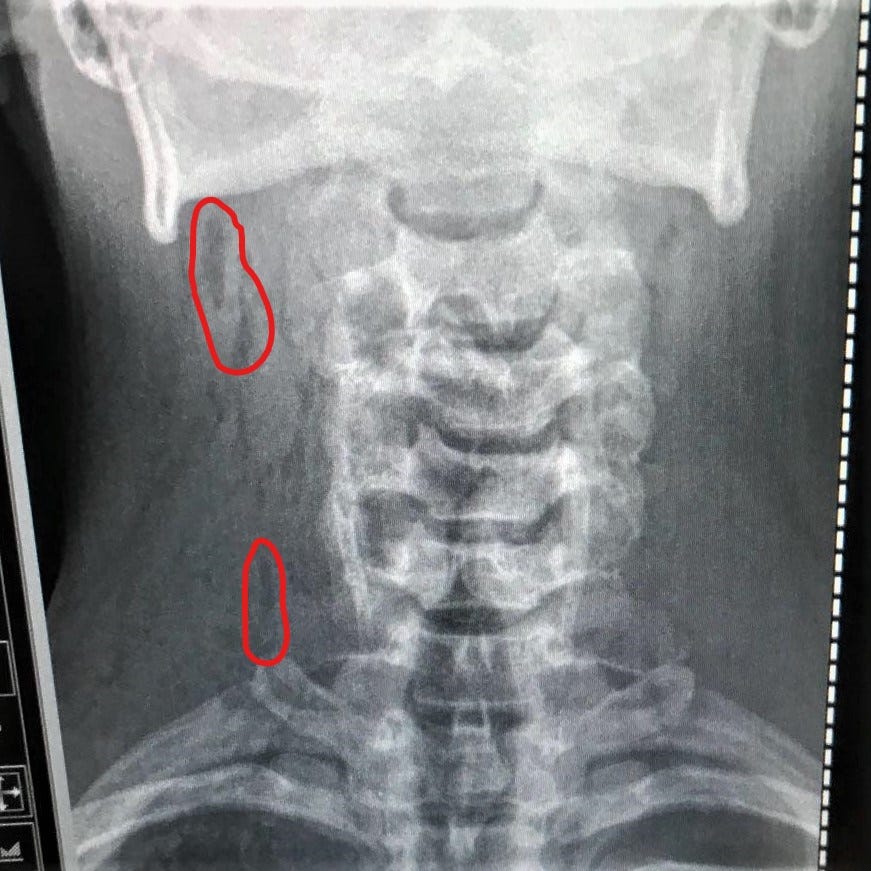

Air Bubble In Lung with preview total 44+ Pictures. It can happen from deep sniffing, drug abuse, and heavy exertion. When that happens, it compresses the lung and does not allow the lung to expand primary spontaneous pneumothorax is when a bulla or air bubble in the lung tissue ruptures and the air makes its way out of the lung and.

Vacuum (negative pressure) holds the lungs tightly against the chest wall lungs slide smoothly and quietly during respiration when filled with air. Air bubble sign was positive in 54 of the patients with pphc (sensitivity 83.1 %) but only 3 of 55 patients in control group (specificity 94.5 %). My mom has been complaining about this pain in her back, assuming it's in her lungs. Lung tumors, which may be harmless.